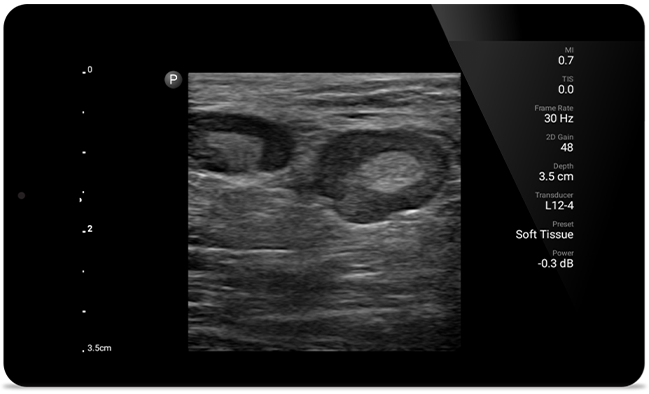

Lumify helps you see the fine details in muscles, joints, ligaments, tendons and cartilage to make a more accurate diagnosis of injuries.

Get the clarity of larger ultrasound systems with Lumify

SonoCT reinforces real tissue imaging while eliminating random artifacts. This technology produces images superior to conventional imaging in up to 94% of patients.